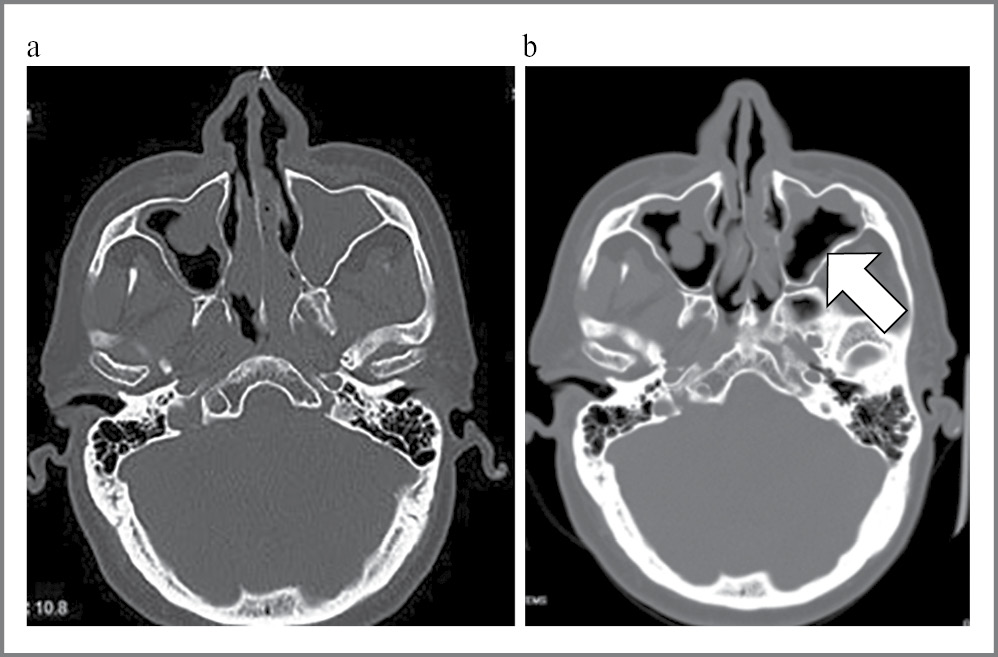

По данным контрольной КТ ППН, через 12 мес проводимой ГИБТ дупилумабом отмечалась существенная положительная динамика в виде сокращения полиповидных разрастаний, уменьшения толщины слизистой оболочки околоносовых пазух, особенно в левой верхнечелюстной пазухе (рис. 1). Отмечалось восстановление пневматизации основной пазухи. Соустья верхнечелюстных пазух были сужены с двух сторон за счет утолщения слизистой. В верхнечелюстных пазухах определялось утолщение слизистой оболочки до 14 мм слева и до 20 мм справа. В ячейках решетчатого лабиринта сохранялось патологическое содержимое до 29 ЕдХ. Значительно уменьшилось утолщение лобных пазух, которое составило не более 4 мм. Носовые ходы были сужены за счет полиповидного утолщения слизистой. Носовая перегородка S-образно искривлена.

Рис. 1. КТ ППН пациента Ф.: a – до терапии дупилумабом; b – через 12 мес терапии дупилумабом. Наблюдается уменьшение тотального заполнения ППН полипозными массами, появляется пневматизация. Особенно отчетливо указанные изменения определяются в левой верхнечелюстной пазухе (стрелка).

Fig. 1. CT of paranasal sinuses of patient's F.: a – before dupilumab therapy; b – after 12 months of dupilumab therapy. There is a decrease in the total filling of paranasal sinuses with polypose masses and aeration appears. The changes are clearly detected in the left maxillary sinus (arrow).